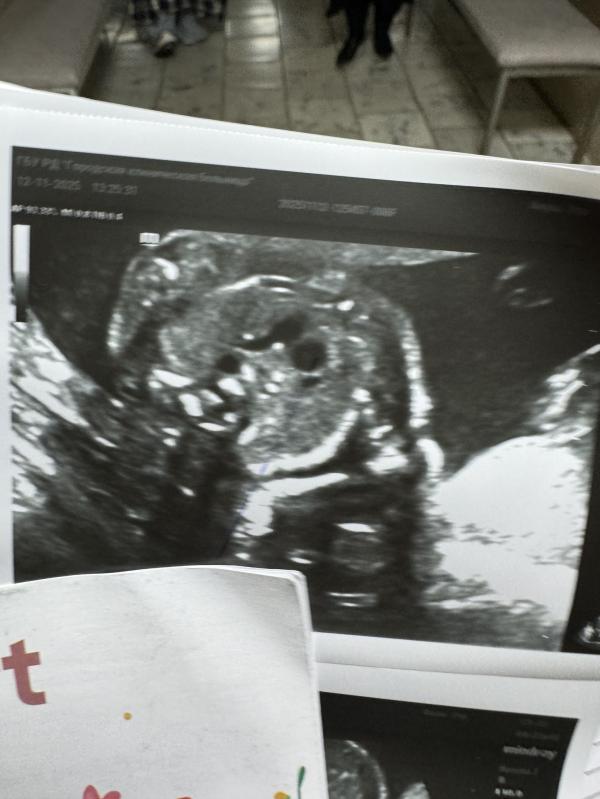

Эта сердце плода получается

Надо на ЭХО-КГ 100% для подтверждения или отпровержения. Расширение аорты - не самая страшная ситуация, у вас отличное четырнхкамерное сердце у малыша, это уже хорошо. Не видят никаких дефектов в перегородках - это тоже отлично. Нужно второе мнение, чтобы вы себя перестали накручивать.